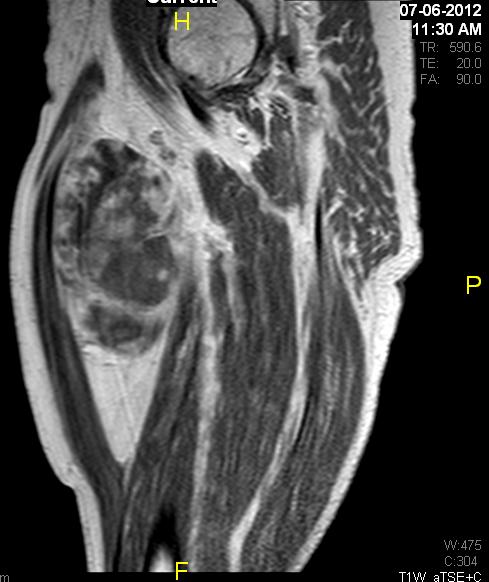

Fig. 7 & 8 Magnetic Resonance Image shows a large heterogeneous mass in the right thigh with low intensity signal on Axial (Fig. 7) and Coronal (Fig. 8) T1-weighted images admixed with high signal areas. The high signal areas represent low grade fatty tissue and low signal the dedifferentiated areas. Higher intensity signal is visible compatible with hemorrhage or necrotic tissue.

Fig. 9 Coronal fat suppressed T1-weigthed MR image demonstrates a large heterogeneous mass in the anterior compartment of the thigh with some areas suppressed corresponding with fatty areas within the tumor. Central hyper enhanced areas compatible with hemorrhage or necrosis.

Fig. 11 – 13 Axial (Fig. 11), Coronal (Fig. 12) and Sagital (Fig. 13) contrasted T1-weighted MR images show a large heterogeneous mass with central and peripheral

enhancement. Multiple thick trabeculations. Central low signal intensity image is compatible with necrosis and hemorrhage.